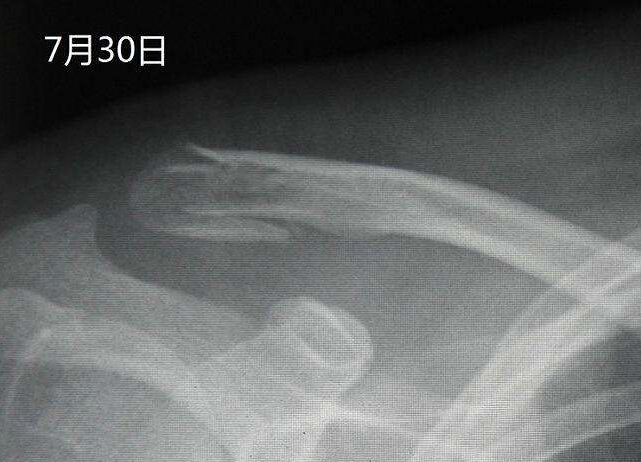

通过拍摄X线片,可以了解骨折的部位,骨折线的走向,骨折的移位情况,骨折的类型等,为医师制定治疗方案,监测治疗结果提供依据。X线照片一般需要拍摄正位和侧位,同时应包括邻近关节,这样才能全面地反映出骨折的全貌。尽管如此,有些骨折还需要加摄特定位置才能显示骨折线,有些骨折需经1~2周后骨折处骨质吸收才能显示骨折线